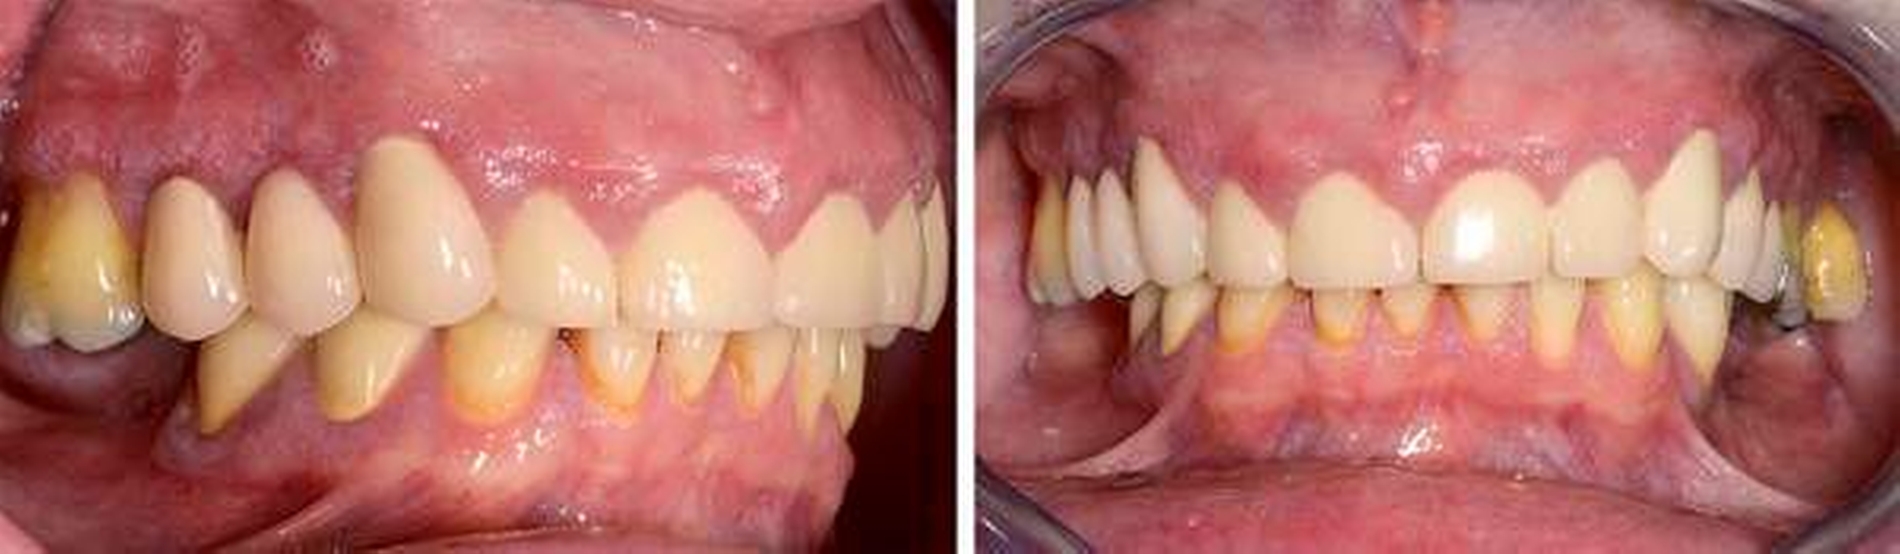

Anamnese: Die 53-jährige Frau stellte sich im Januar 2015 in der Poliklinik für Parodontologie des Universitätsklinikums Dresden vor. Sie war von ihrer Hauszahnärztin mit der Bitte um Diagnostik und Therapie der gingivalen Größenzunahmen (Abbildungen 1a bis 1e) überwiesen worden. Die Patientin gab an, dass die Vergrößerung der Gingiva vor ungefähr einem Jahr begonnen habe und diese sie mittlerweile in ihrer häuslichen Mundhygiene einschränke. Die Benutzung von Hilfsmitteln zur Interdentalraumpflege sei nicht mehr möglich und die Gingiva blute seitdem häufig. Den Kaukomfort ihres 2009 angefertigten Zahnersatzes empfand sie als gut. Als Grund für die multiplen endodontischen Therapien und die Überkronungen an den Zähnen 15, 13 bis 22 sowie 24 und 25 gab die Patientin starke Abrasionen an. Seit dem Auftreten der Gingivawucherungen ergänzte sie auf Anraten ihrer Hauszahnärztin die häusliche Mundhygiene einmal täglich mit Chlorhexidingel, 1-prozentig.

Befund: Bei der klinischen Untersuchung zeigten sich vestibulär und oral im Bereich der Papillen und der befestigten Gingiva generalisierte Gingivawucherungen im Oberkiefer (OK) und im Unterkiefer (UK). Die Interdentalräume waren aufgrund der Gingivawucherungen nicht für Hygienehilfsmittel durchgängig. Der Parodontale Screeningindex (PSI) wies im OK die Codes 3/3/4, im UK die Codes 3/1/3 auf. Der daraufhin erhobene Parodontalstatus (Abbildung 2) zeigte im OK Sondierungstiefen bis 7 mm mit Furkationsbeteiligungen Grad I (Zähne 16, 26, 27). Im UK betrugen die Sondierungstiefen bis zu 4 mm. Die Zahnbeweglichkeit an den Zähnen 16, 26 (Grad I) und 27 (Grad II) war erhöht.

Sechs Wochen nach Deep Scaling und Root Planing erfolgte eine zweite Reevaluation mit Befunderhebung [MacNeil RL et al., 1999]. Erhöhte Sondierungstiefen lagen nur noch an den Zähnen 27 (5 mm) und 34 (4 mm) vor (Abbildung 4). Die Gingivawucherungen hatten sich vollständig zurückgebildet (Abbildungen 5a bis 5e). Die Plaque- und Blutungsindizes waren niedrig und stabil (20 Prozent). Abschließend wurde eine PZR zusammen mit einer subgingivalen Reinigung an den Zähnen 27 und 34 durchgeführt. Die Prognose der Zähne mit Ausnahme des Zahns 27 ist weiter als sicher einzustufen. Zahn 27 bleibt kritisch. Dies ist durch den Attachmentverlust von 10 mm mesial und den Lockerungsgrad II begründet. Aufgrund der kompromittierenden parodontalen Situation und der eingeschränkten prothetischen Wertigkeit könnte bei Beschwerden an Zahn 27 neben einer chirurgischen Taschenelimination auch eine Extraktion erwogen werden. Die bisherige prothetische Versorgung könnte dann im Konzept einer verkürzten Zahnreihe belassen werden [Fueki K et al., 2015; Levey C et al. 2015]. Da die Patientin vorerst keine weitere Therapie an Zahn 27 wünschte, musste an dieser Stelle von einer chirurgischen Taschenelimination abgesehen und der Zahn belassen werden.